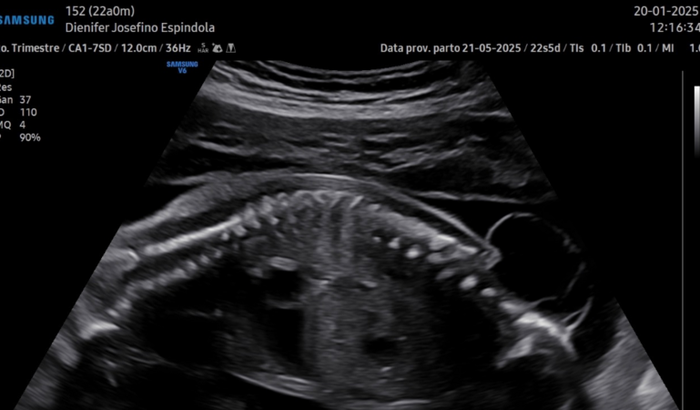

Olá, sou a Dienifer, criei essa vakinha pois estou grávida e minha neném está com uma malformação na coluna(espinha bífida), onde é necessário fazer uma cirurgia intrauterina que custa em torno de R$180.000,00. Agradeço no que puder ajudar. ver tudo

Olá, sou a Dienifer, criei essa vakinha pois estou grávida e minha neném está com uma malformação na coluna(espinha bífida), onde é necessário fazer uma cirurgia intrauterina que custa em torno de R$180.000,00. Agradeço no que puder ajudar.